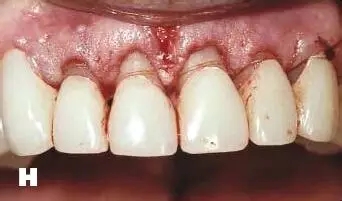

牙周炎發(fā)展到一定階段時(shí),僅采用基礎(chǔ)治療難以取得較好療效,必須通過(guò)適時(shí)而合宜的手術(shù)治療挽救患牙,才能保持牙周組織健康,延長(zhǎng)患牙在口腔內(nèi)的壽命,維持牙列的完整性,促進(jìn)全身健康。其手段包括齦下刮治、根面平整、牙周翻瓣術(shù)、牙齦切除術(shù)、牙周夾板固定術(shù)等。

牙齒松動(dòng)疼痛妨礙修復(fù)體咀嚼功能、炎癥性的牙周組織損害基牙、牙周炎癥時(shí)牙齒位置不穩(wěn)定、牙齦炎癥未消除取模不準(zhǔn)確、修復(fù)體冠邊緣必須建立在健康牙齦溝內(nèi),通過(guò)修復(fù)治療,恢復(fù)牙周組織功能。對(duì)于能夠保留的松動(dòng)牙齒,有必要進(jìn)行松牙固定術(shù)。